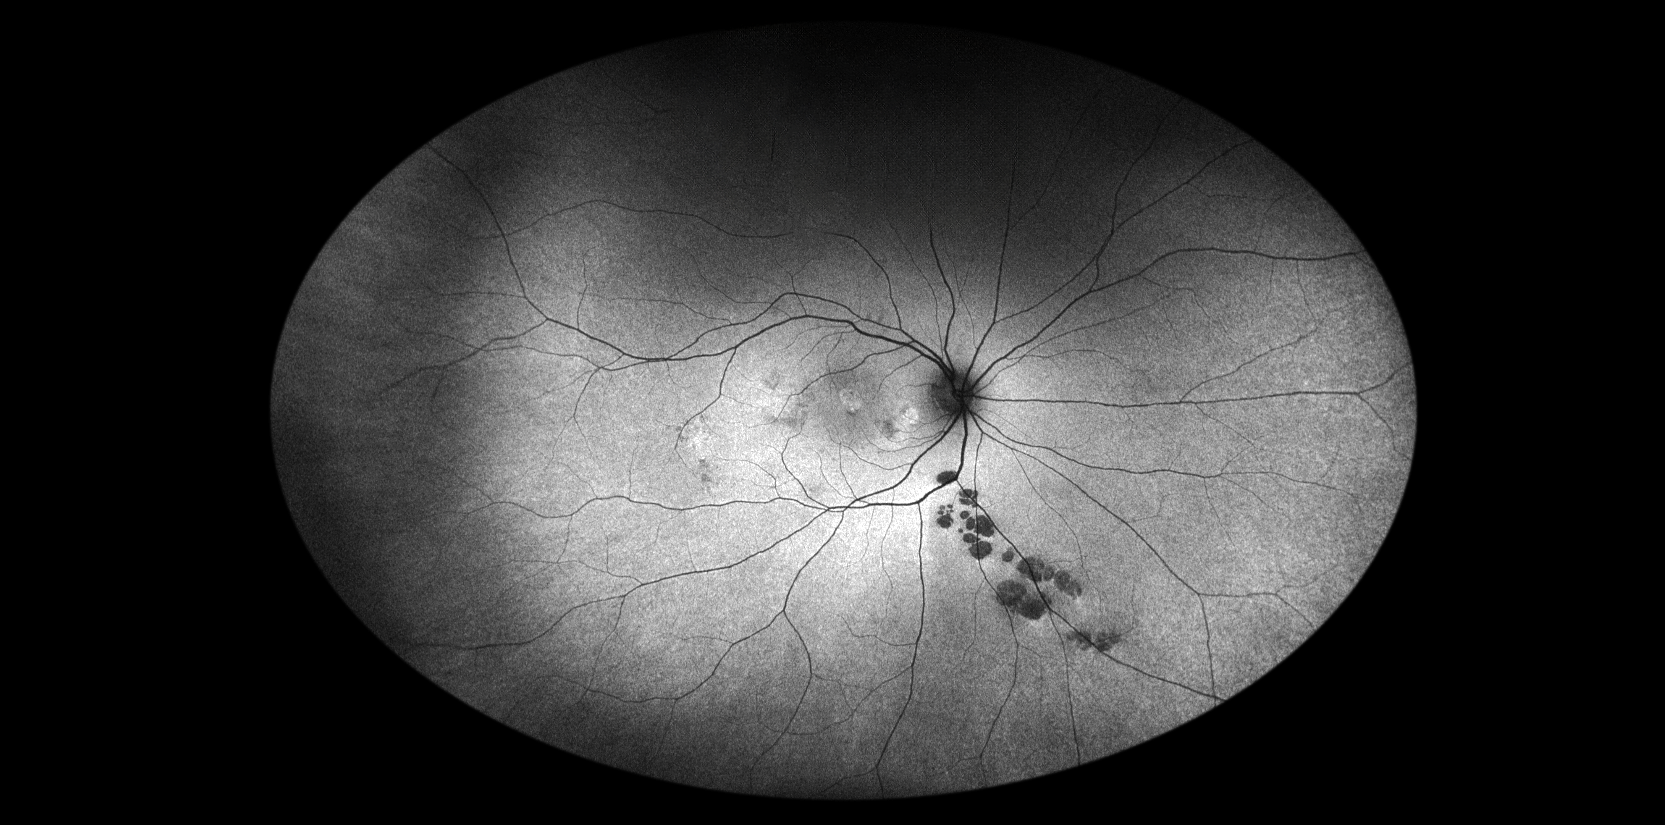

Bear Tracks Presented by Katherine Pippin, CRA This photograph received Third Place, Autoflourescence in the 2025 OPS Scientific Exhibit. Filed Under Retina OPS Photo